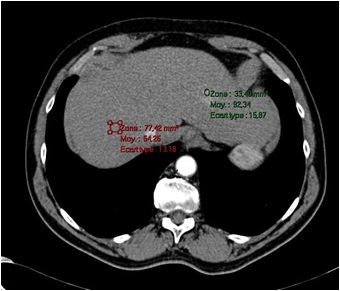

1. 第一个主要的特征:多血管性(early arterial uptake)

还有很多的图示来解释这一过程  在影像上的表现是动脉期增强

增强CT扫描,在动脉后期显示的增强病变应该考虑肝癌的可能性,虽然和造影剂注射速率、造影剂浓度和早期肝癌发现有关。敏感性高,而特异性差。

2. 第二个主要特点是 wash-out (清除)(wash-out in the portovenous and equilibrium phase)